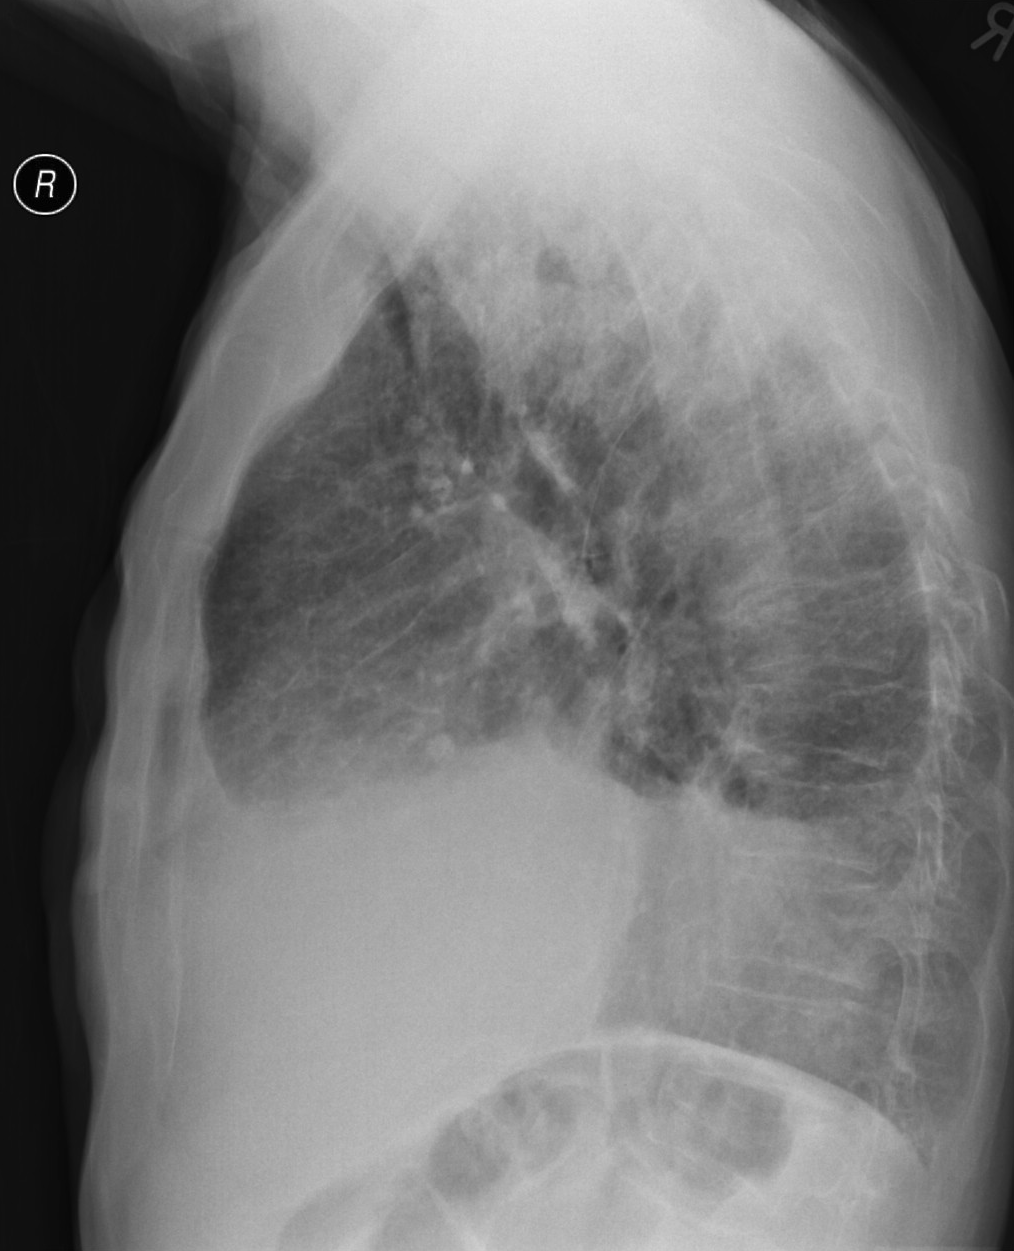

19. Tuberculosis, bidirectional chest radiographs and HRCT. (coronal reconstruction)

75 year old man: hx of hypertension, smoking. Symptoms: dyspnea, productive cough. Moist rales of auscultatory findings above the LLL, tension irritability in the level of lower dorsal spine.

a.) Chest radiograph, bilateral: Mild increased vascular markings. Extensive patchy lobar infiltration in the RUL Previous TB specific lesions in the left apex. The diaphragm contour is blurry on the right side (appr. 4 finger-wide pleural effusion). Cardiomegaly. Medium large dilated sclerotic aorta.

b.) HRCT: Reticular pattern of 10x10x5 cm area in the right apex (1st segment), (septal thickenings), mosaic-like ground glass opacity in the righ apex. Subpleural total atelectasis (mainly 1st segment): irregular mainly nodular soft tissue streak associated with the pleura (max. appr. 1 cm thickness). Some tiny subpleural emphysematous bullae in the right apex.